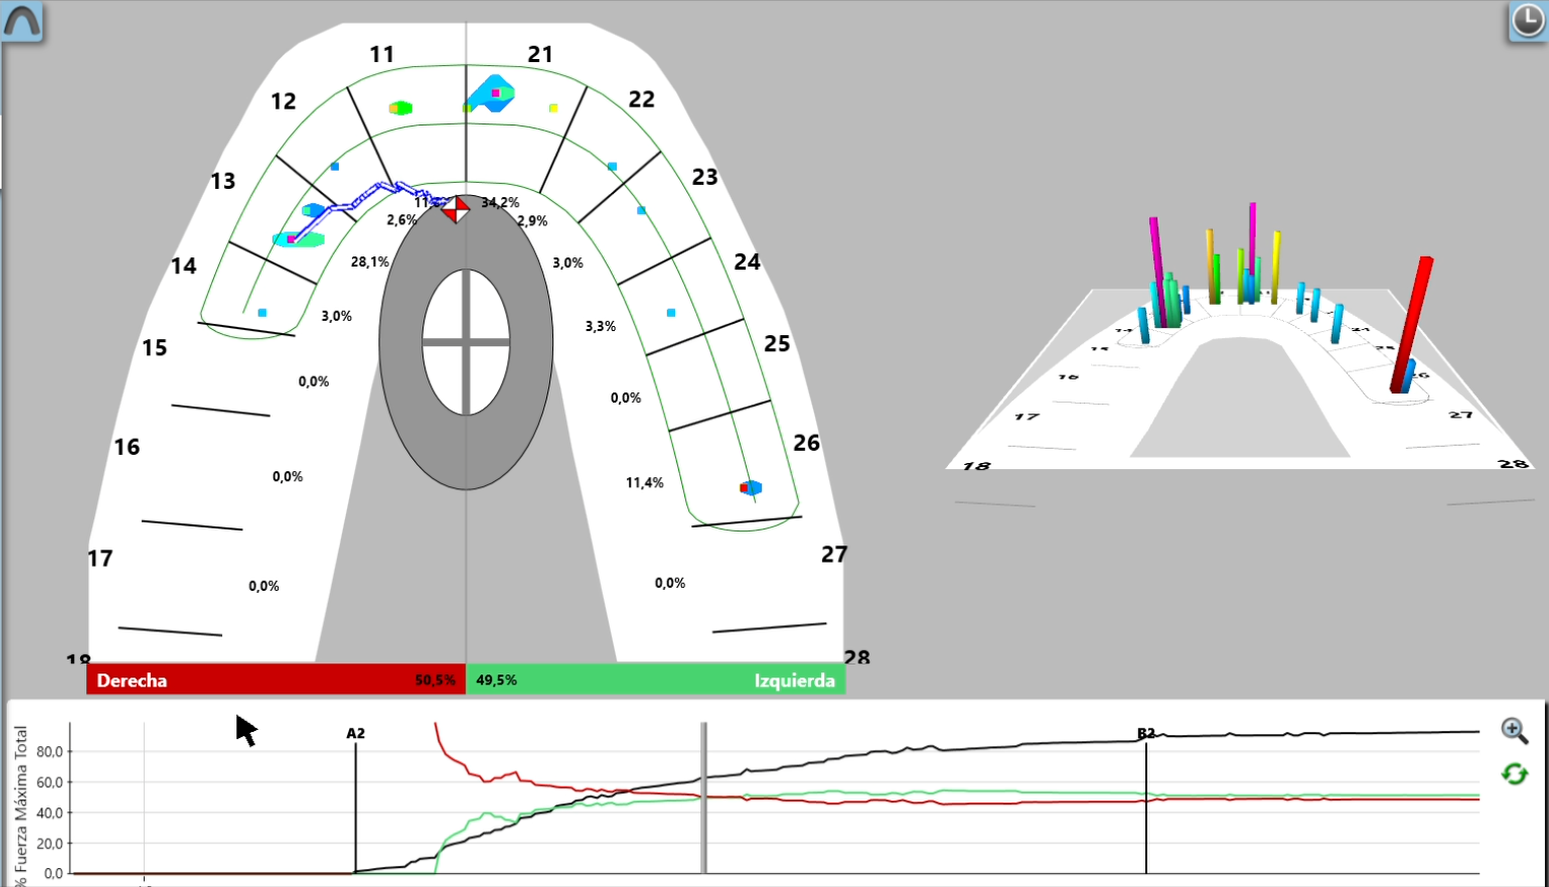

T-scan

Con sistemas de jaw tracking y oclusión digital de última tecnología como T-Scan, alcanzamos un nivel de precisión sin precedentes en el diagnóstico y tratamiento de problemas dentales y de la articulación temporomandibular (ATM).